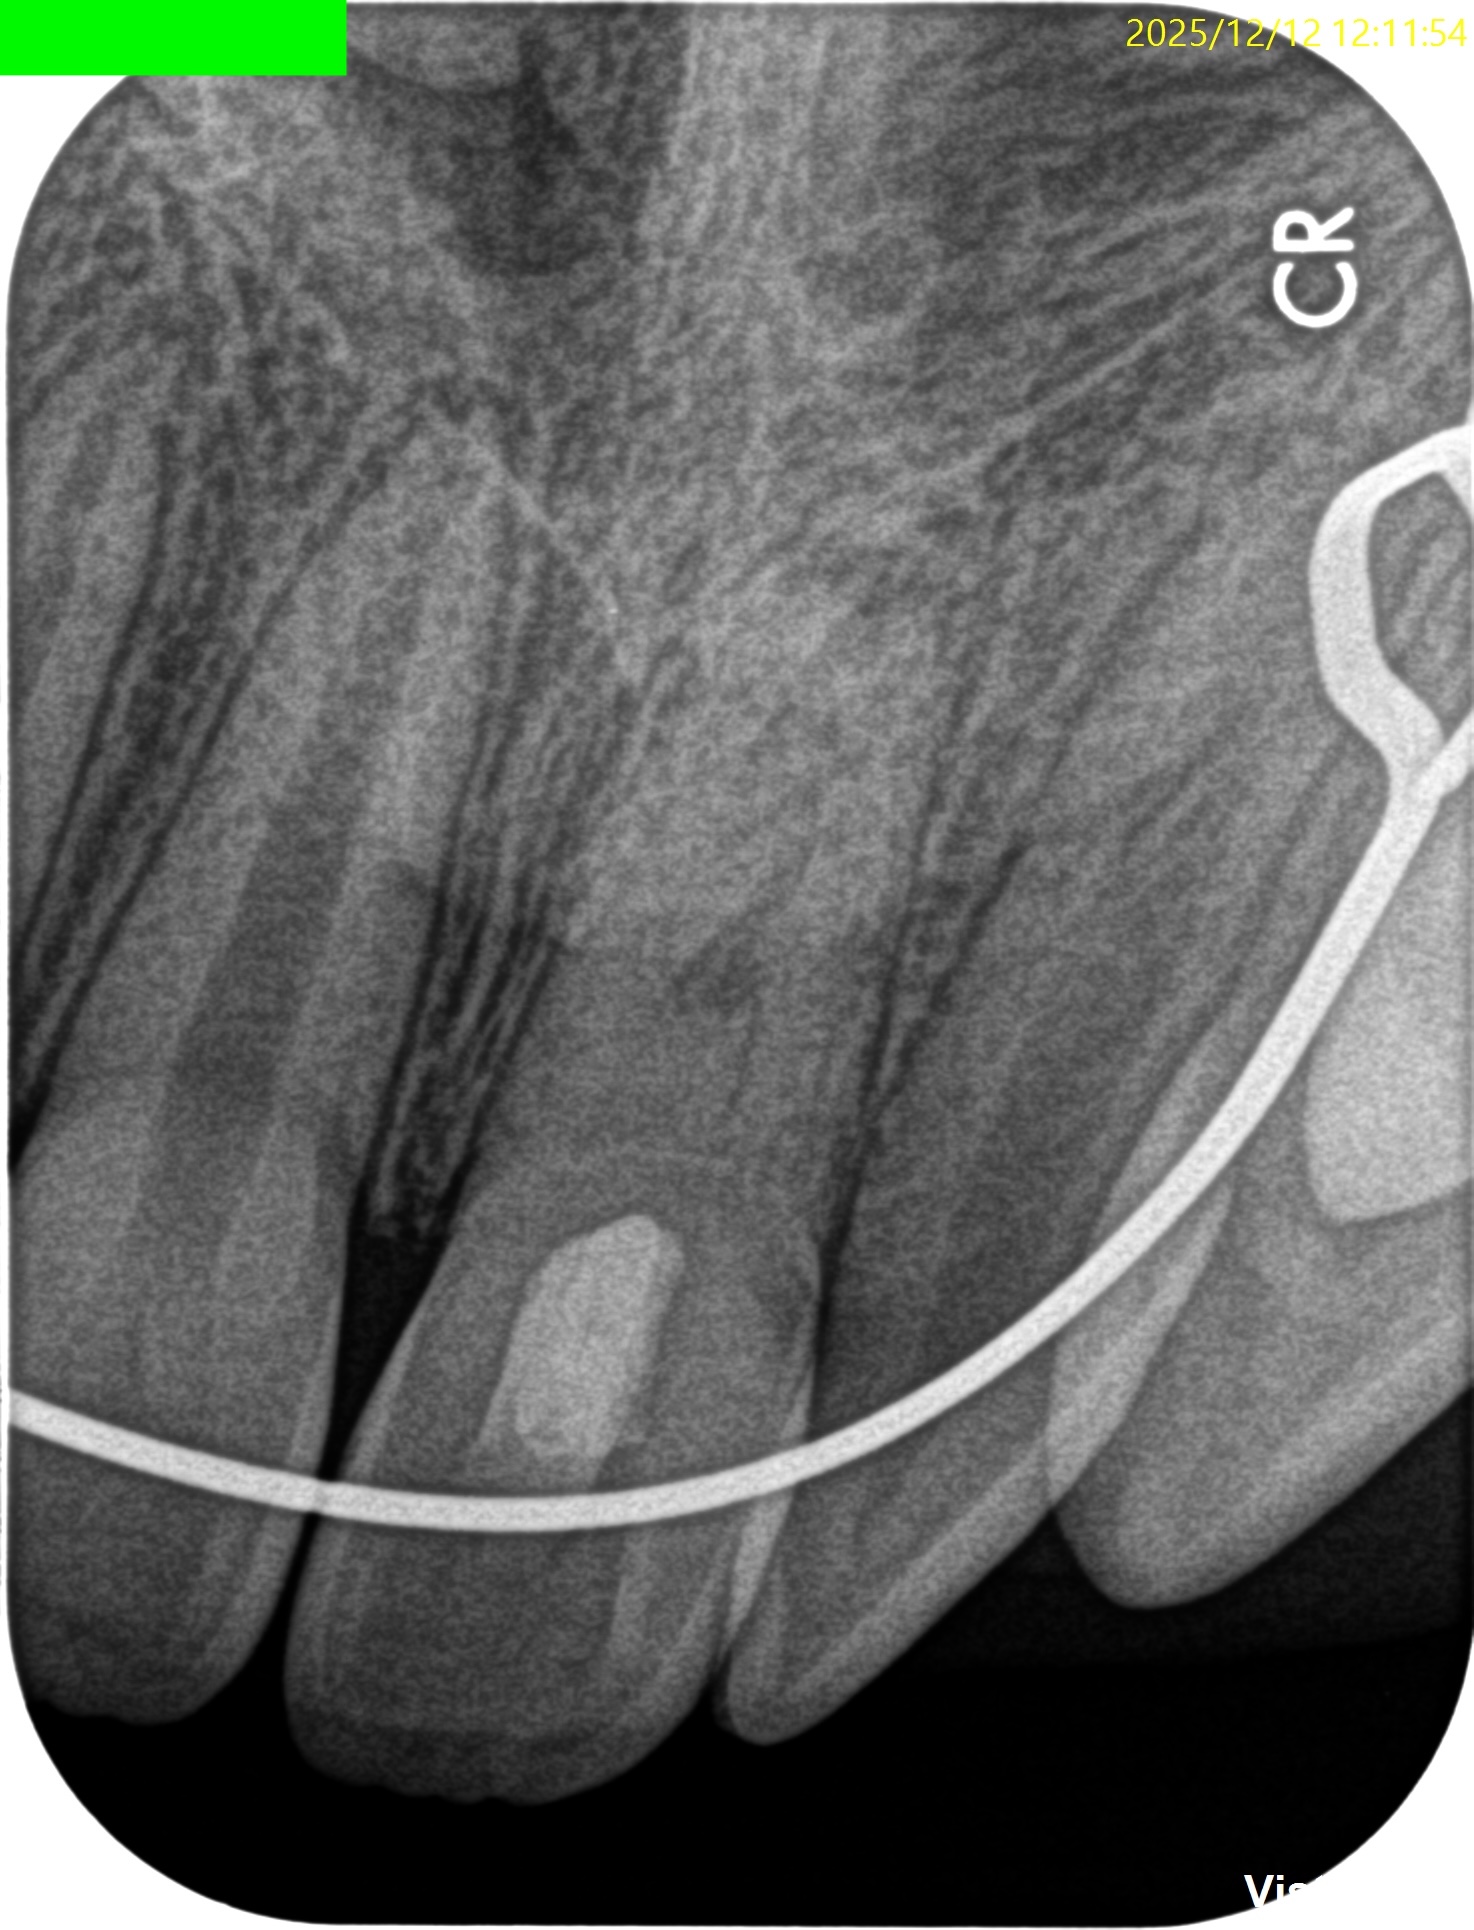

#9 Regeneration 2yr recall(2025.12.12)

ちなみに#8は、

根が完成している。

初診時、1年経過観察時と比較した。

大きく問題が解決している。